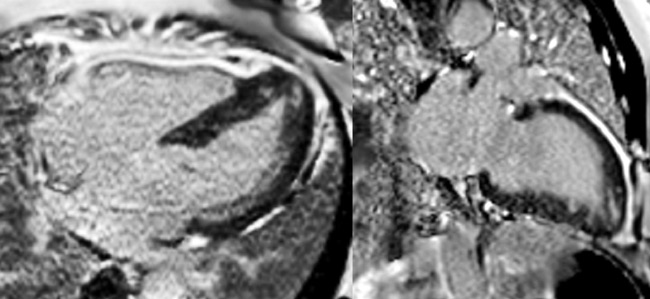

Figure 3 : Séquence de Réhaussement tardif

Coupes petit-axe

Figure 4 : Séquence de Réhaussement tardif

Coupes long-axe 4 cavités et 2 cavités

Cardiomyopathie hypertrophique (CMH) sarcomérique à FEVG préservée avec :

- Obstruction intra-VG sous-aortique

- Systolic anterior motion (SAM) partiel

- Nodules de fibrose dense aspécifique dans les régions hypertrophiées apicales

Pour comprendre :

- La topographie centro-myocardique du rehaussement tardif correspond à une fibrose dense aspécifique qui ne serait pas liée à une cardiopathie ischémique (sinon le rehaussement tardif aurait été sous-endocardique), ou à un processus inflammatoire type myocardite (sinon le rehaussement tardif aurait été sous-épicardique).

- La présence de l’obstruction intra-VG et du SAM partiel invite à optimiser le traitement médical de la CMH.

- La présence des nodules de fibrose dense aspécifique traduit un risque de troubles du rythme ventriculaire plus élevé à prendre en compte dans la prise en charge ; a fortiori chez ce patient hospitalisé pour syncope d’effort…